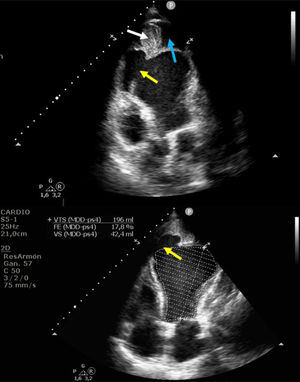

Presentamos el caso de una paciente de 61años con infarto de miocardio evolucionado hace un mes, que presentó complicaciones mecánicas postinfarto. La ecocardiografía evidenció un pseudoaneurisma apical de gran tamaño (fig. 1 y fig. 3: fecha azul) (Vídeo Anexo 1), con cuello de 2,93cm (fig. 1 y fig. 2: flecha amarilla) y paso de ecocontraste libre a su través (fig. 2: fecha roja), con la luz parcialmente trombosada (fig. 1 y fig. 3: fecha blanca). Se observó también un ventrículo izquierdo severamente dilatado y disfunción sistólica global muy severa (fig. 1) (FEVI 11%, IVT TSVI 7cm). A las 48horas de ingreso la paciente desarrolló shock cardiogénico SCAIC-D, que requirió soporte mecánico con ECMOV-A y balón de contrapulsación intraaórtico, logrando una notable mejoría de la perfusión orgánica. Tras coordinación con el hospital de referencia, fue trasplantada cardiaca código0, con una recuperación favorable. Este caso destaca la importancia del diagnóstico ecocardiográfico y el manejo con soporte mecánico en situaciones críticas de shock cardiogénico.